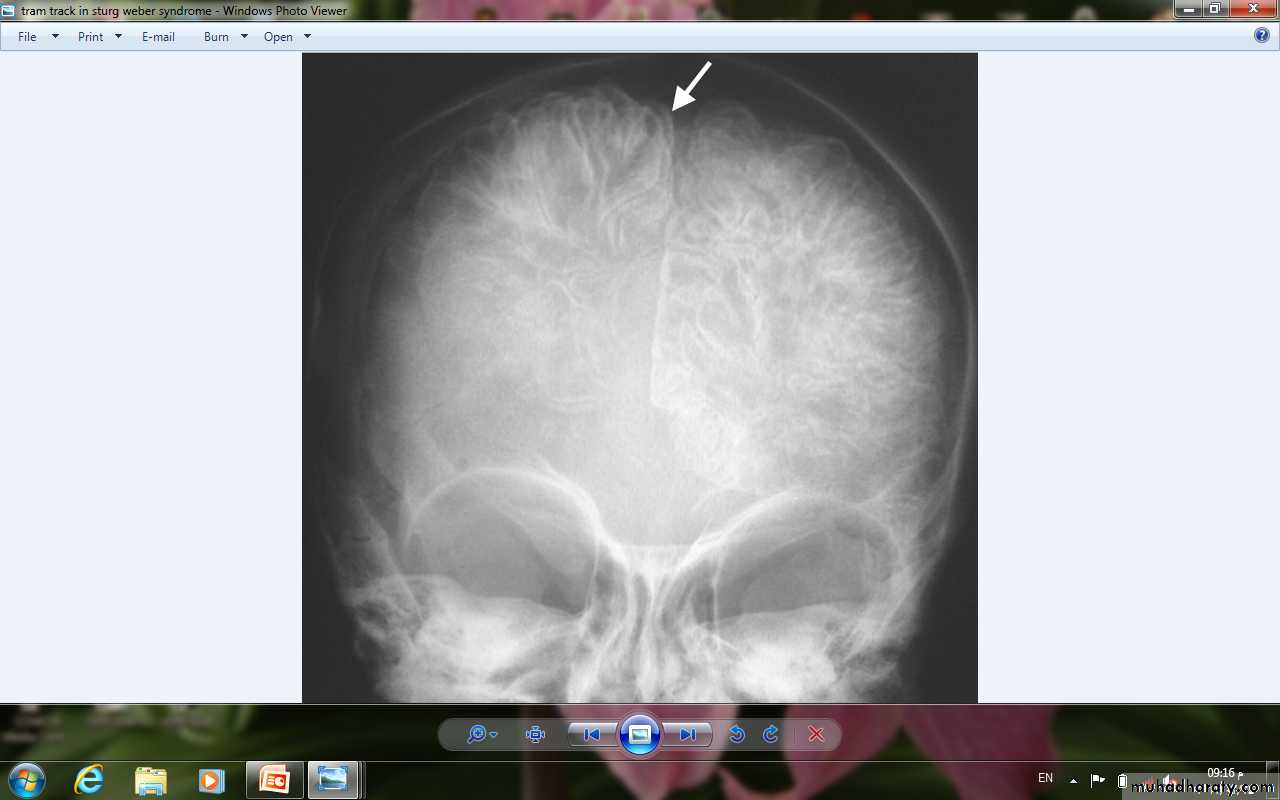

• 1- Skull x-ray: shows intracranial calcification in the occipitoparietal region in most patients. This characteristically assumes railroad-track appearance.

•